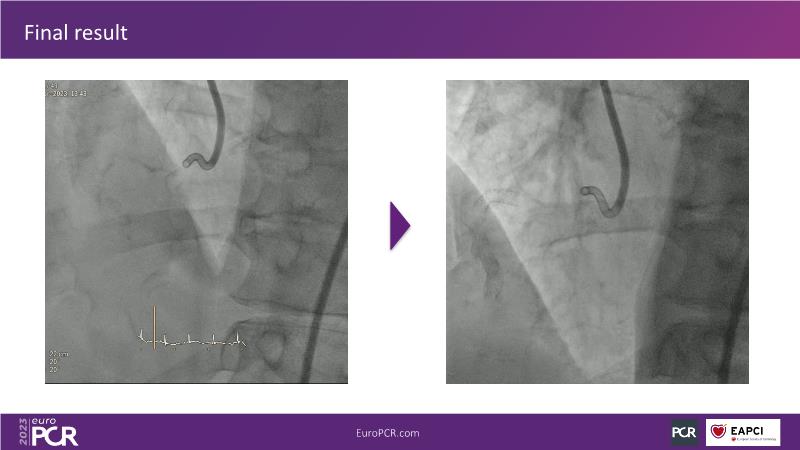

Robotic PCI: real-life experience with a new robotic platform

The current problems in interventional cardiology have been the same for years: exposure to X-rays, or orthopaedic injuries to operators after decades in the cathlab. The solution to these problems could lie in robotics and the increasing use of artificial intelligence in practice. Follow this session on the future of robotics to learn more about the benefits it could bring.